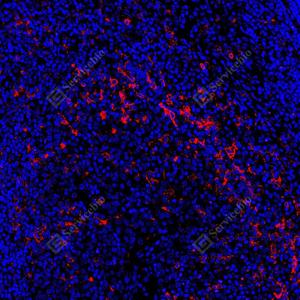

| IF检测CD14蛋白(货号 GB15254)(红色). 样品: 人食管癌, 4%多聚甲醛 (货号G1101) 固定12-24小时. 抗原修复: 抗原修复仪(货号 ARI-4),Tris-EDTA抗原修复液(pH 9.0) (货号G1203), 水浴100℃, 25分钟. 封闭: 3% BSA(货号GC305010)的PBS溶液, 室温孵育30分钟. —抗: 1: 500稀释, 4℃ 孵育过夜. 二抗: Cy3标记山羊抗小鼠IgG (H+L) (货号GB21301), 1: 300稀释, 室温孵育1小时. |

| IF检测CD14蛋白(货号 GB15254)(红色). 样品: 人肝癌, 4%多聚甲醛 (货号G1101) 固定12-24小时. 抗原修复: 抗原修复仪(货号 ARI-4),Tris-EDTA抗原修复液(pH 9.0) (货号G1203), 水浴100℃, 25分钟. 封闭: 3% BSA(货号GC305010)的PBS溶液, 室温孵育30分钟. —抗: 1: 500稀释, 4℃ 孵育过夜. 二抗: Cy3标记山羊抗小鼠IgG (H+L) (货号GB21301), 1: 300稀释, 室温孵育1小时. |